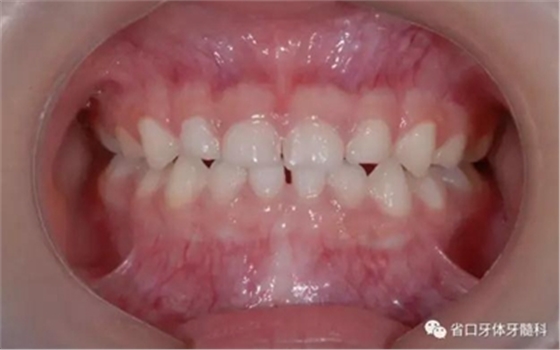

圖13 矯治結(jié)束后正面牙相(2015年3月)

圖11 局部牙性前牙反合可使用頜墊舌簧糾正

頜墊舌簧適用于局部乳前牙反合的矯治或者替牙期局部前牙反合治療。